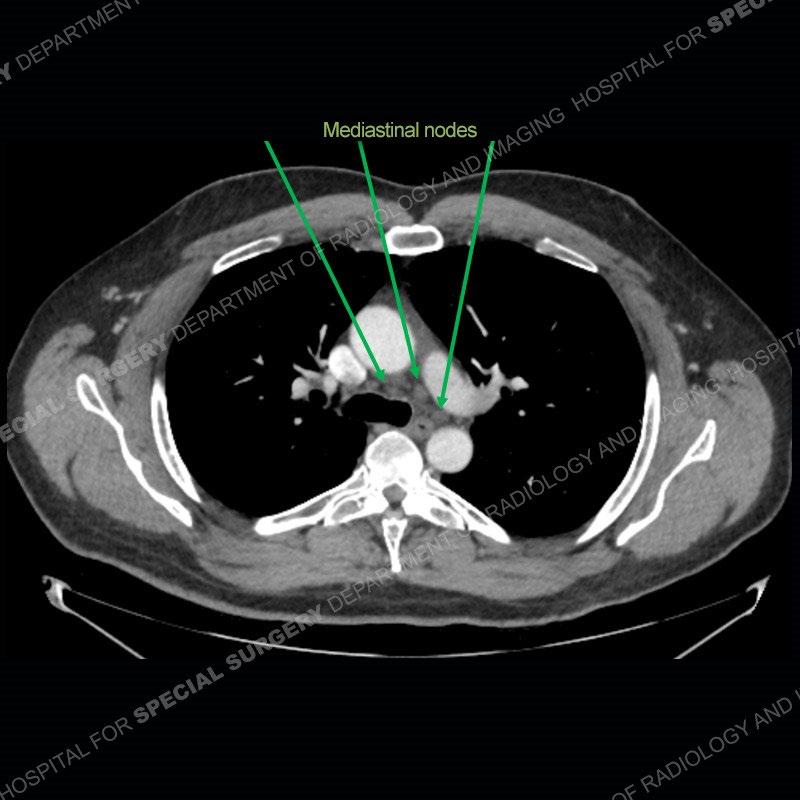

The chest radiographs demonstrate a leftward deviation of the trachea. CT images demonstrate a large, somewhat heterogeneous mass of the thyroid that extends outside the confines of the thyroid tissue. There is a subtle, enhancing soft tissue mass of the proximal right humerus. Slightly prominent mediastinal lymph nodes are present with additionally, multiple supraclavicular lymph nodes.

Although not strictly a part of the evaluation of an “incidental” thyroid lesion, evaluation of the adjacent lymph nodes and bony structures can also be quite important. In this case, there is an enhancing mass of the right humerus. This is very subtle and can only really be recognized by evaluating the density of the bone. Typicaly marrow will have a fatty density or nearly fluid density. As the density, as in this case, approaches soft tissue an infiltrative process must be entertained. Thyroid mets are markedly vascular accounting for the areas of enhancement of the humeral mass. The mediastinal and supraclavicular lymph nodes although not individually enlarged, should raise suspicion of an underlying inflammatory/neoplastic process.